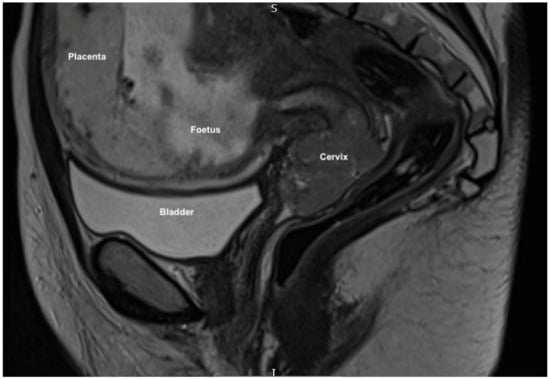

2.2. Clinical Findings

2.3. Diagnostic Assessment